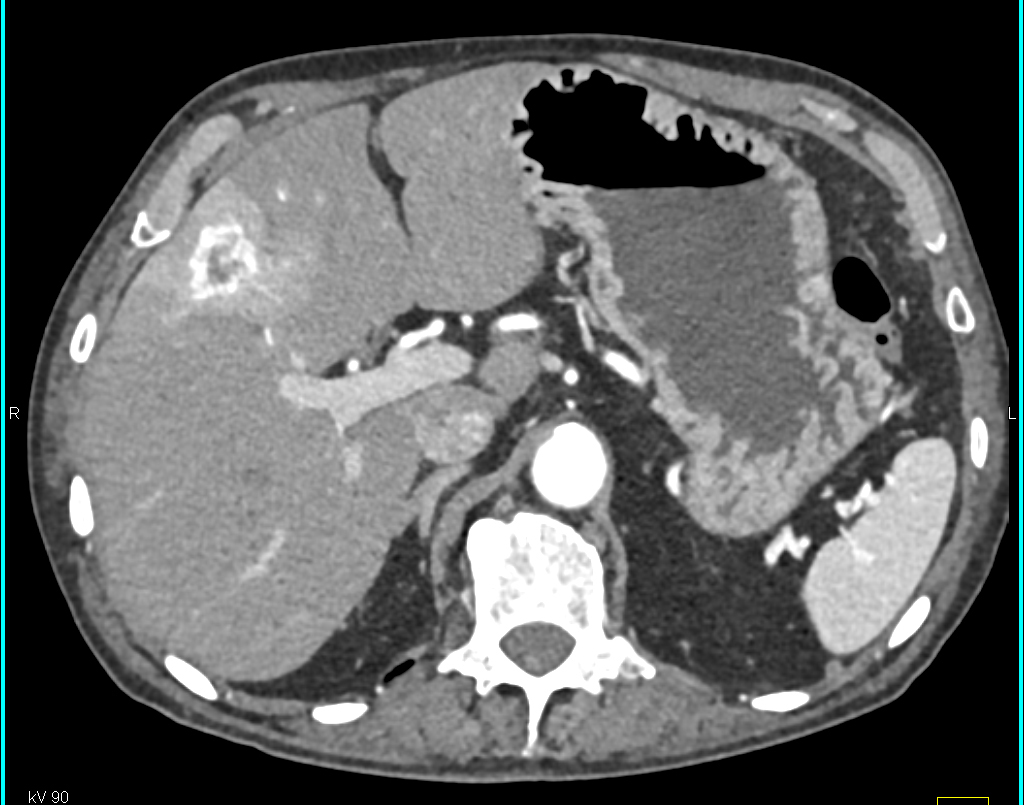

The best diagnosis in this case is?

metastatic PNET tumor

carcinoid tumor

hemangioma

hepatoma